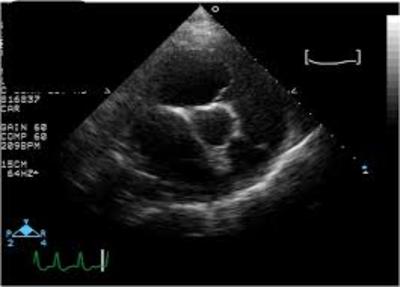

Question

Which image below is of an ECHO on the long axis?